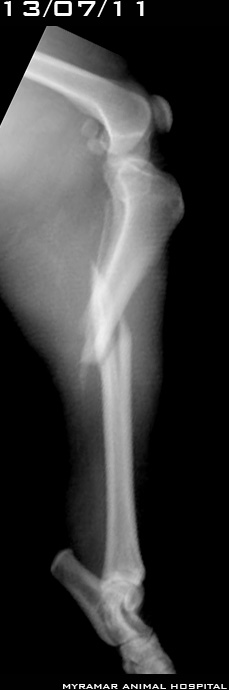

Mora, perrita cruzada de 8 años y 23 kg de peso, es remitida por cojera de extremidad posterior derecha de varios meses de evolución. Al estudio radiográfico se observa degeneración osteoartrósica de la articulación de la rodilla y signos evidentes de lesión crónica de ligamento cruzado anterior. Mora fue operada hace 3 años de su rodilla izquierda por rotura de dicho ligamento.

Se realiza TPLO con placa synthes para tornillos bloqueados LHS.

Se presentan radiografías pre y posquirúrgicas del caso.